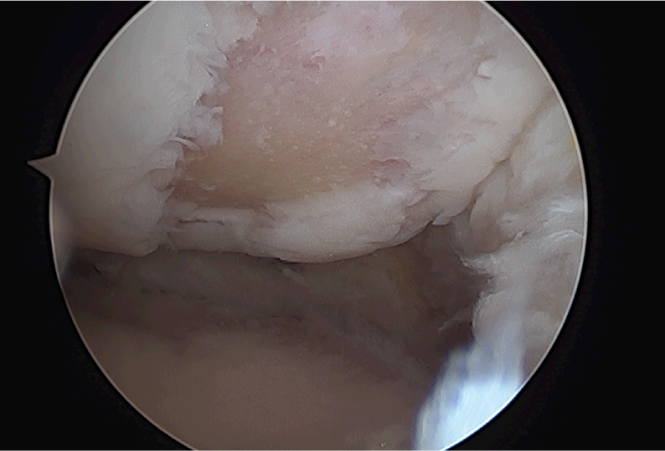

반월상 연골이란 무릎 관절 내부에서 체중분산 및 관절 연골 보호 관절내 윤활 기능을 하는 구조물로 반월상 연골판은 퇴행 변화 및 과격한 운동으로 손상을 입게 되며 피가 통하지 않는 부위라 스스로 치유가 매우 어렵고 추가적인 파열이 진행되게 됩니다.

파열된 연골

수술후